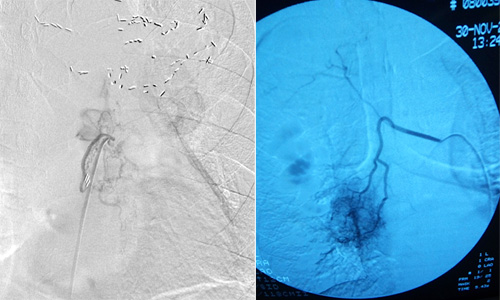

医院呼吸内一科介入团队根据病症情况,成功为该患者实施经支气管动脉灌注化疗栓塞术。手术精准、微创、无痛,全过程仅需局部麻醉,患者术后一天即可下床行走。

中晚期肺癌难以采取手术切除,尽管化疗药物和放疗技术的不断更新,传统的放、化疗的有效率还是非常低。支气管动脉灌注化疗栓塞术是在患者腹股沟区用穿刺针作直径几毫米的微小通道,然后把化疗药物通过导管直接输送到肿瘤,进行局部精准化疗,浓度可以达到静脉化疗药物浓度的400倍以上,对肿瘤的杀伤力很强,同时其全身反应要小于静脉给药。给药完成后,也可栓塞肿瘤血管,阻断肿瘤的血供营养,从而“饿死”肿瘤,达到“治、控”结合的治疗目的。